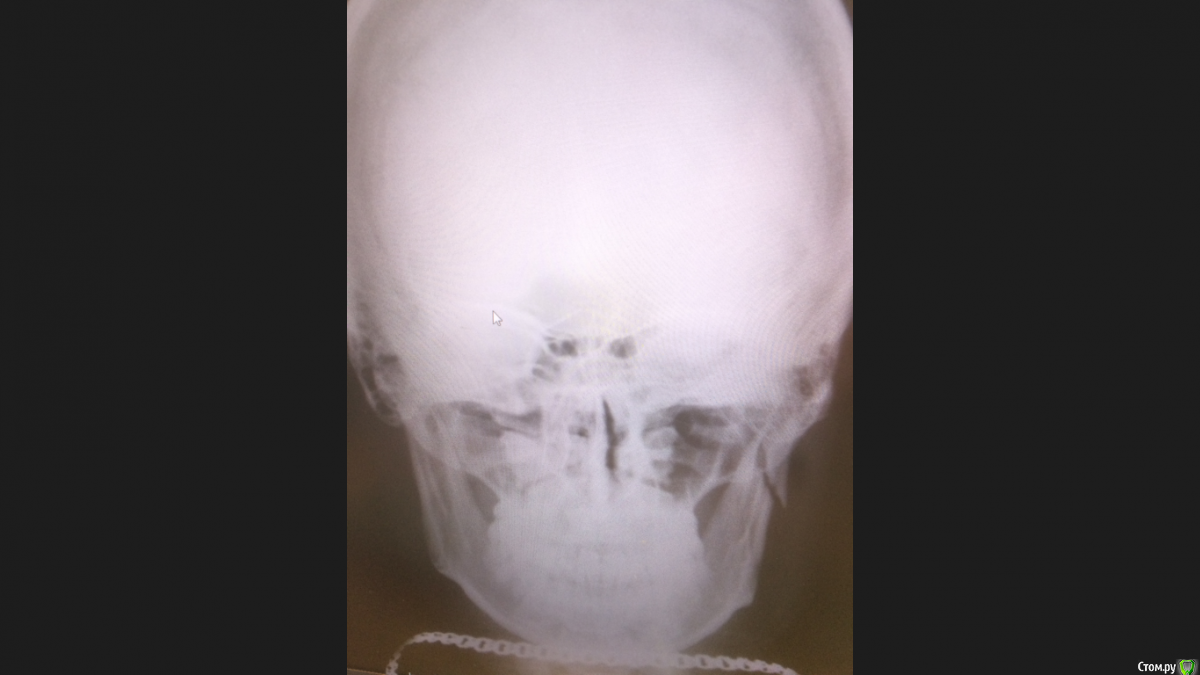

Как то Так Опубликовано 22 декабря, 2017 Автор Поделиться Опубликовано 22 декабря, 2017 Уважаемые врачи,прошу Вас посмотреть мой снимок сделанный 22.12.2017 ,очень интересно ваше мнение так как в выписке с стационара написано что шины нужно снимать 22.12.2017.нормально срастается и вообще как быть ? перелом вроде как не беспокоит ,единственно что ночью бывает довольно часто что как бы нижняя челюсть съезжает в глубь рта,и вроде по ощущениям что не попадает зуб на зуб,после чего я ее как бы сам легким усилием ставлю в обратное (удобное ) положение - что меня и беспокоит,нормально ли это? Ссылка на комментарий

Irouil Опубликовано 22 декабря, 2017 Поделиться Опубликовано 22 декабря, 2017 Советую сделать КТ.На данный момент снимок мне не нравится, к тому же эта подвижность... Надо посмотреть в полости рта и снаружи. Создаётся впечатление, что потребуется операция. 1 Ссылка на комментарий

Irouil Опубликовано 22 декабря, 2017 Поделиться Опубликовано 22 декабря, 2017 Оценка реабилитации после перелома зависит от восстановления функции. Челюсть должна двигаться в том диапазоне и по тем же траекториям, что до перелома. Рот открывается, закрывается, жуёт, говорит и т.д. При том положении, которое занимает суставная головка на Вашем снимке я не представляю как она будет производить все необходимые движения. Варианта два: либо они будут ограничены, при крепком срастании перелома, но в неправильном положении, либо они будут лишними, при не плотном сращении перелома ("ложный сустав"). Однако, конечно же Вашим лечащим врачам виднее, ибо в реальности организм способен удивлять в самых разных ситуациях 1 Ссылка на комментарий